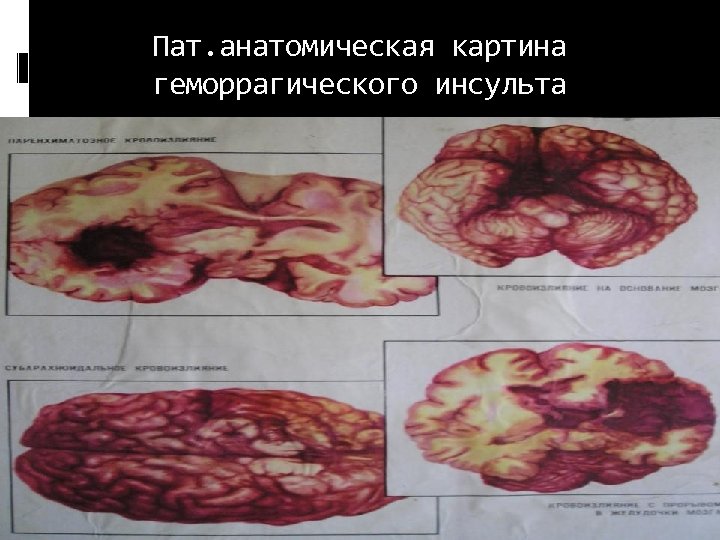

Патоморфология геморрагических инсультов Кровоизлияния по типу гематомы – кровоизлияния, образованием сопровождающиеся полости, содержащей жидкую кровь или кровяные сгустки, составляют основную геморрагических инсультов (85%). массу

Патоморфология геморрагических инсультов Кровоизлияния по типу гематомы – кровоизлияния, образованием сопровождающиеся полости, содержащей жидкую кровь или кровяные сгустки, составляют основную геморрагических инсультов (85%). массу

Пат. анатомическая картина геморрагического инсульта

Пат. анатомическая картина геморрагического инсульта